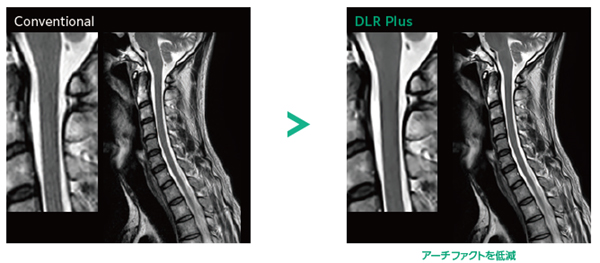

Deep Learning Reconstruction

SNRや鮮鋭度をあとからコントロール

Deep Learning技術を活用し※1,撮像終了後の画質調整を可能に。SNRを最適化するほか,MRI信号の処理を段階的に行うことで(k空間上の信号処理の工夫)画像の鮮鋭度を向上させます。これにより超解像度化やトランケーションアーチファクトを低減します。